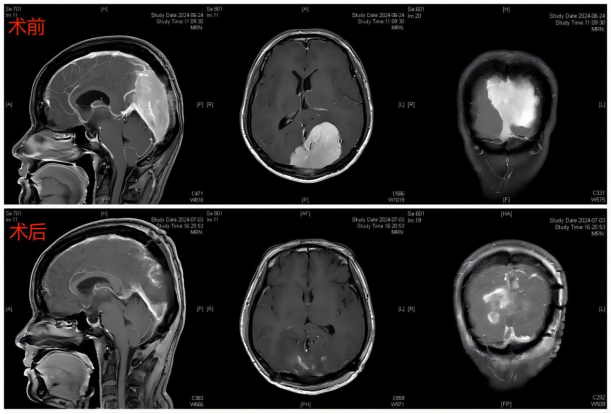

▲术前术后磁共振对比

(完整切除肿瘤)

术后复查磁共振提示患者颅内肿瘤全切。术后不到1周,患者即恢复至术前状态,并未有任何神经功能障碍,术后10天,患者带着感激与开心的心情顺利出院。